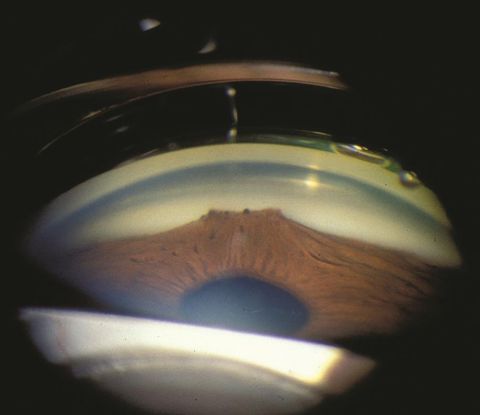

Slit-lamp biomicroscopy shows variable changes to the pupillary ruff, ranging from sectoral pigmentation at the pupillary margin, to a complete, flat pigmented ring around the pupil, extending variably toward the angle. The pupil itself may be distorted in shape and size due to traction, and the central opening may be displaced (corectopia).[20]

Gonioscopy may show new vessels in the angle of the anterior chamber, and anterior synechiae may be present.[21]